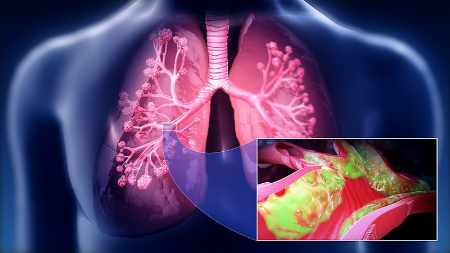

• هامارتومای ریوی (در ریهها)

هامارتومای ریوی شایعترین نوع آن است

۳٫ هامارتومای ریه چقدر شایع است؟

شایعترین هامارتومای خوشخیم ریه است (حدود ۷۰–۸۰٪ تومورهای خوشخیم ریه).

بیشتر در بزرگسالان ۴۰–۶۰ سال دیده میشود و در مردان شایعتر است.